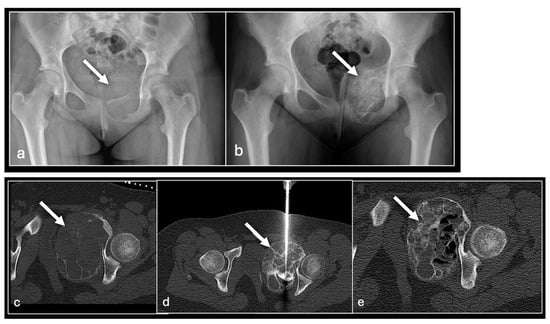

Figure 4. AP radiograph of pelvis (a) showing destructive lesion of left pubis and superior pubic ramus (arrow) with marked consolidation post three sessions of sclerotherapy (b). Axial CT imaging pre sclerotherapy (c), intraprocedural (d), and following three sessions of sclerotherapy (e) to the lesion (arrow).

The cyst is typically accessed using an 11 G bone biopsy needle. If the lesion is multiloculated, the needle is agitated to break up the septations to facilitate communication and its contents are aspirated. The position is confirmed with the injection of iodinated contrast which also has the benefit of confirming no intravascular communication or leak into other adjacent structures is present as also described in the existing literature [28,29]. If the lesion cannot be completely opacified, further punctures may be required. Once satisfactorily opacified, the sclerosant is injected and subsequently aspirated to minimise the risk of leakage. This allows the lesion to consolidate or involute over successive procedures (Figure 4 and Figure 5).

Sclerotherapy advantageously does not suffer from the risks to adjacent tissues and skin seen with the thermoablation techniques described above. Complication rates are low but sclerosant leakage or injection into vascular structures is a potential risk which can lead to embolism and tissue necrosis. Perhaps the biggest drawback is that repeat procedures are frequently necessary, particularly for larger lesions resulting in substantial time and resource allocation [30,31,32].